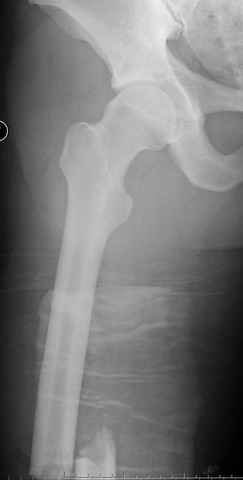

больному 42, автоавария, политравма, открытая черепномозговая травма, безсознании, открытый перелом бедра, размозжение мягких тканей, дефект кожи на передней поверхности бедра около 13 см2 от ожога, компартмент синдром.

По поводу открытого перелома больной ургентно взят на ретроградное интрамедулярное штифтование, после рутинного дебрайдмента и фасциотомии на бедре и на голени.

перелом бедра

постоперационные